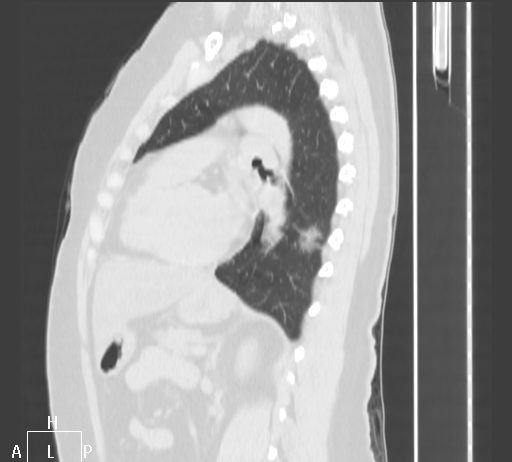

Paziente di 78 anni con febbre e tosse da una settimana ed insufficienza respiratoria (saturazione 84).

TC torace